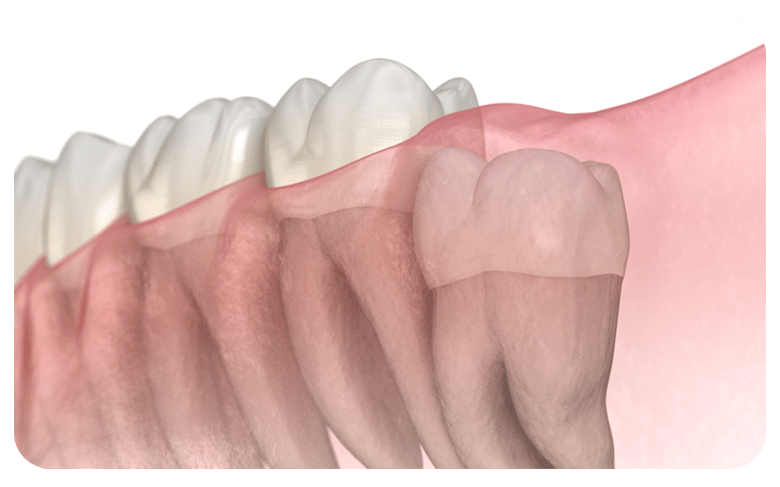

매복사랑니란?

사랑니가 완전히 맹출 되지 않고 잇몸 아래 묻혀있는

형태의 사랑니를  매복 사랑니라고 합니다.

사랑니가 완전히 맹출 되지 않고 잇몸 아래에 묻혀있는 형태의 사랑니를 매복 사랑니라고 합니다.

매복 사랑니는 함치성낭종, 염증 유발, 턱뼈 손상 등의 문제를 유발할 수 있어 발치해주는 것이 좋습니다.

부분매복

수직매복

원심경사 매복

수평매복